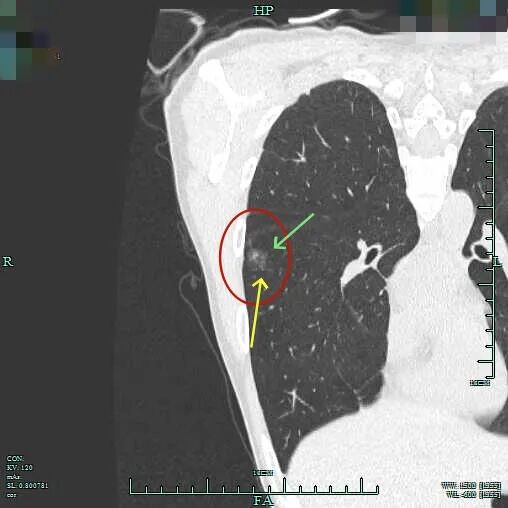

指南上说优先处理主病灶,兼顾次病灶,在不影响生存及符合无瘤原则前提下尽量切除病灶并尽可能保留肺功能。次病灶若是纯GGO,受限于心肺功能无法全部切除时,建议6-12个月随访1次。也就是说:如果心肺功能吃得消,即便次病灶是纯GGO,也是应该尽量切除。这个原则也是宣扬“一网打尽”处理肺结节的医生的指导性原则。但我总觉得指南也是人定的、脱胎于临床研究与回顾分析得出的结论肯定会落后于疾病的发展与时代的变化、疾病谱的改变,从而不一定适应临床。死守指南会导致患者肺功能受损明显、创伤太大、费用过高,而且无法解决导致多发病灶的机体内环境与外环境因素,从而难以避免后续随访中再检出新的病灶。所以我一直宣扬“抓大放小”。今天分享的这个病例右侧较为明显的有四处病灶,主病灶A在右下叶靠近叶间裂,次病灶一处在右上叶病灶B,一处在右下病灶C,还有一处密度很淡的病灶D是邻近病灶B的。我们是如何决策与考虑的?

非薄层上右下主病灶A有微小血管进入,距离胸膜近,表面不平,灶内密度稍不均。

薄层上病灶出现,靠叶间裂处密度高呈实性成分,边上是磨玻璃成分,轮廓较清。